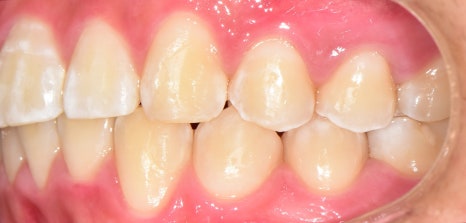

구강 사진을 보면

윗니가 뻐드러져 있는 걸 볼 수 있으며

아랫니는 치열이 고르지 못한 것을 알 수 있었습니다.

정면과 측면에서 봤을 때

하악 전치부가 거의 보이지 않을 정도로

심한 과개 교합을 양상을 나타내고 있었습니다.

전체적으로

문제점을 종합해 보면

2급 부정교합과 과개 교합을 나타내고 있었습니다.

인비절라인 후

구내 사진을 보여드리겠습니다

처음에 보이지 않던

하악 전치부=아래턱 앞니가

이제는 ‘잘’ 보이는 것을 확인해 볼 수 있습니다.

고르지 못했던 치열도

바르게 개선되면서 ‘U’ Shape를 나타냈으며

안쪽 면에 설측 유지 장치를 붙여드리게 되었습니다.